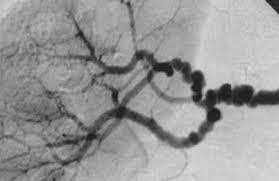

What is the appearance of polyarteritis nodosa on imaging

String-of-pearls appearance

Early lesion weaken the wall leading to aneurism

Late lesions heal with fibrosis